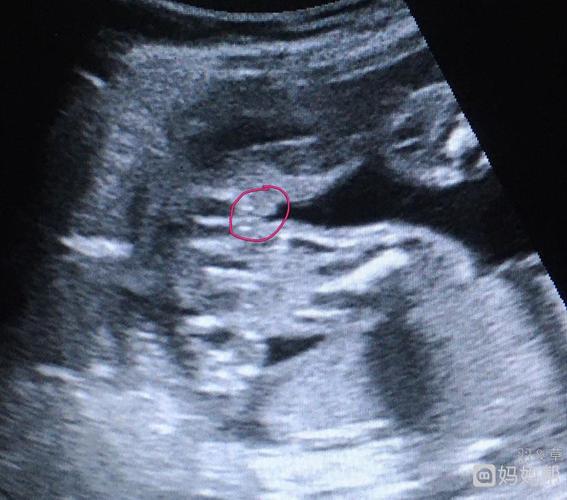

这是传说中的四维三线女宝图吗?这个位置是

四维突然发现了这个,这是不是女宝的标志